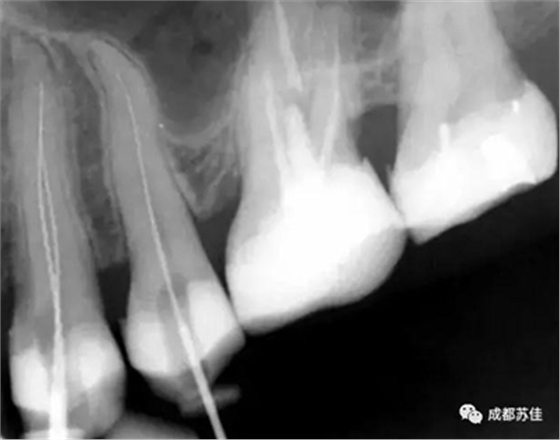

(2)超高空間分辨率及密度分辨率影像板完美的保證了成像質(zhì)量

Compass 2 使用最高敏感性和最智能的IP板讀取技術(shù)來獲取最高質(zhì)量的影像此外,Compass 2 允許減少曝光時間,從而減少欠曝和過曝。

空間分辨率最高可達16.7lp/mm,16位(65,636)的灰度,能夠可靠的分辨出D1級別的齲損及細小至ISO 06 級別的根管器械。

灰度值可自動調(diào)整,無需反復(fù)更改曝光設(shè)置也可獲得持續(xù)性的影像結(jié)果,影像讀取后只需微調(diào)即可獲得良好的影像減少過曝引起的偶然性。